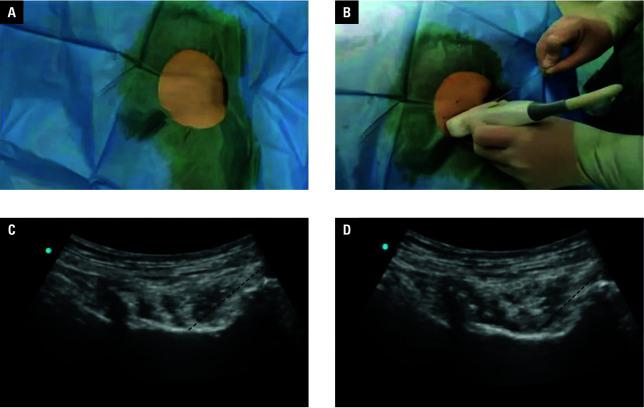

We aimed to assess the effects of ultrasound‑guided pericapsular nerve group block (PENGB) coupled with laryngeal mask airway (LMA) general anesthesia on anesthetic efficacy in elderly patients suffering from FNF undergoing closed reduction and internal fixation (CRIF), as well as their postopera‑ tive analgesia and rapid recovery.

Control group (n = 47) and study group (n = 57) were established for FNF patients hospitalized between October 2022 and August 2023, based on different anesthesia modes. Ultrasound‑guided fascia iliaca compartment block (FICB) and LMA general anesthesia were offered to the control group, while the study group underwent ultrasound‑guided PENGB and LMA general anesthesia.